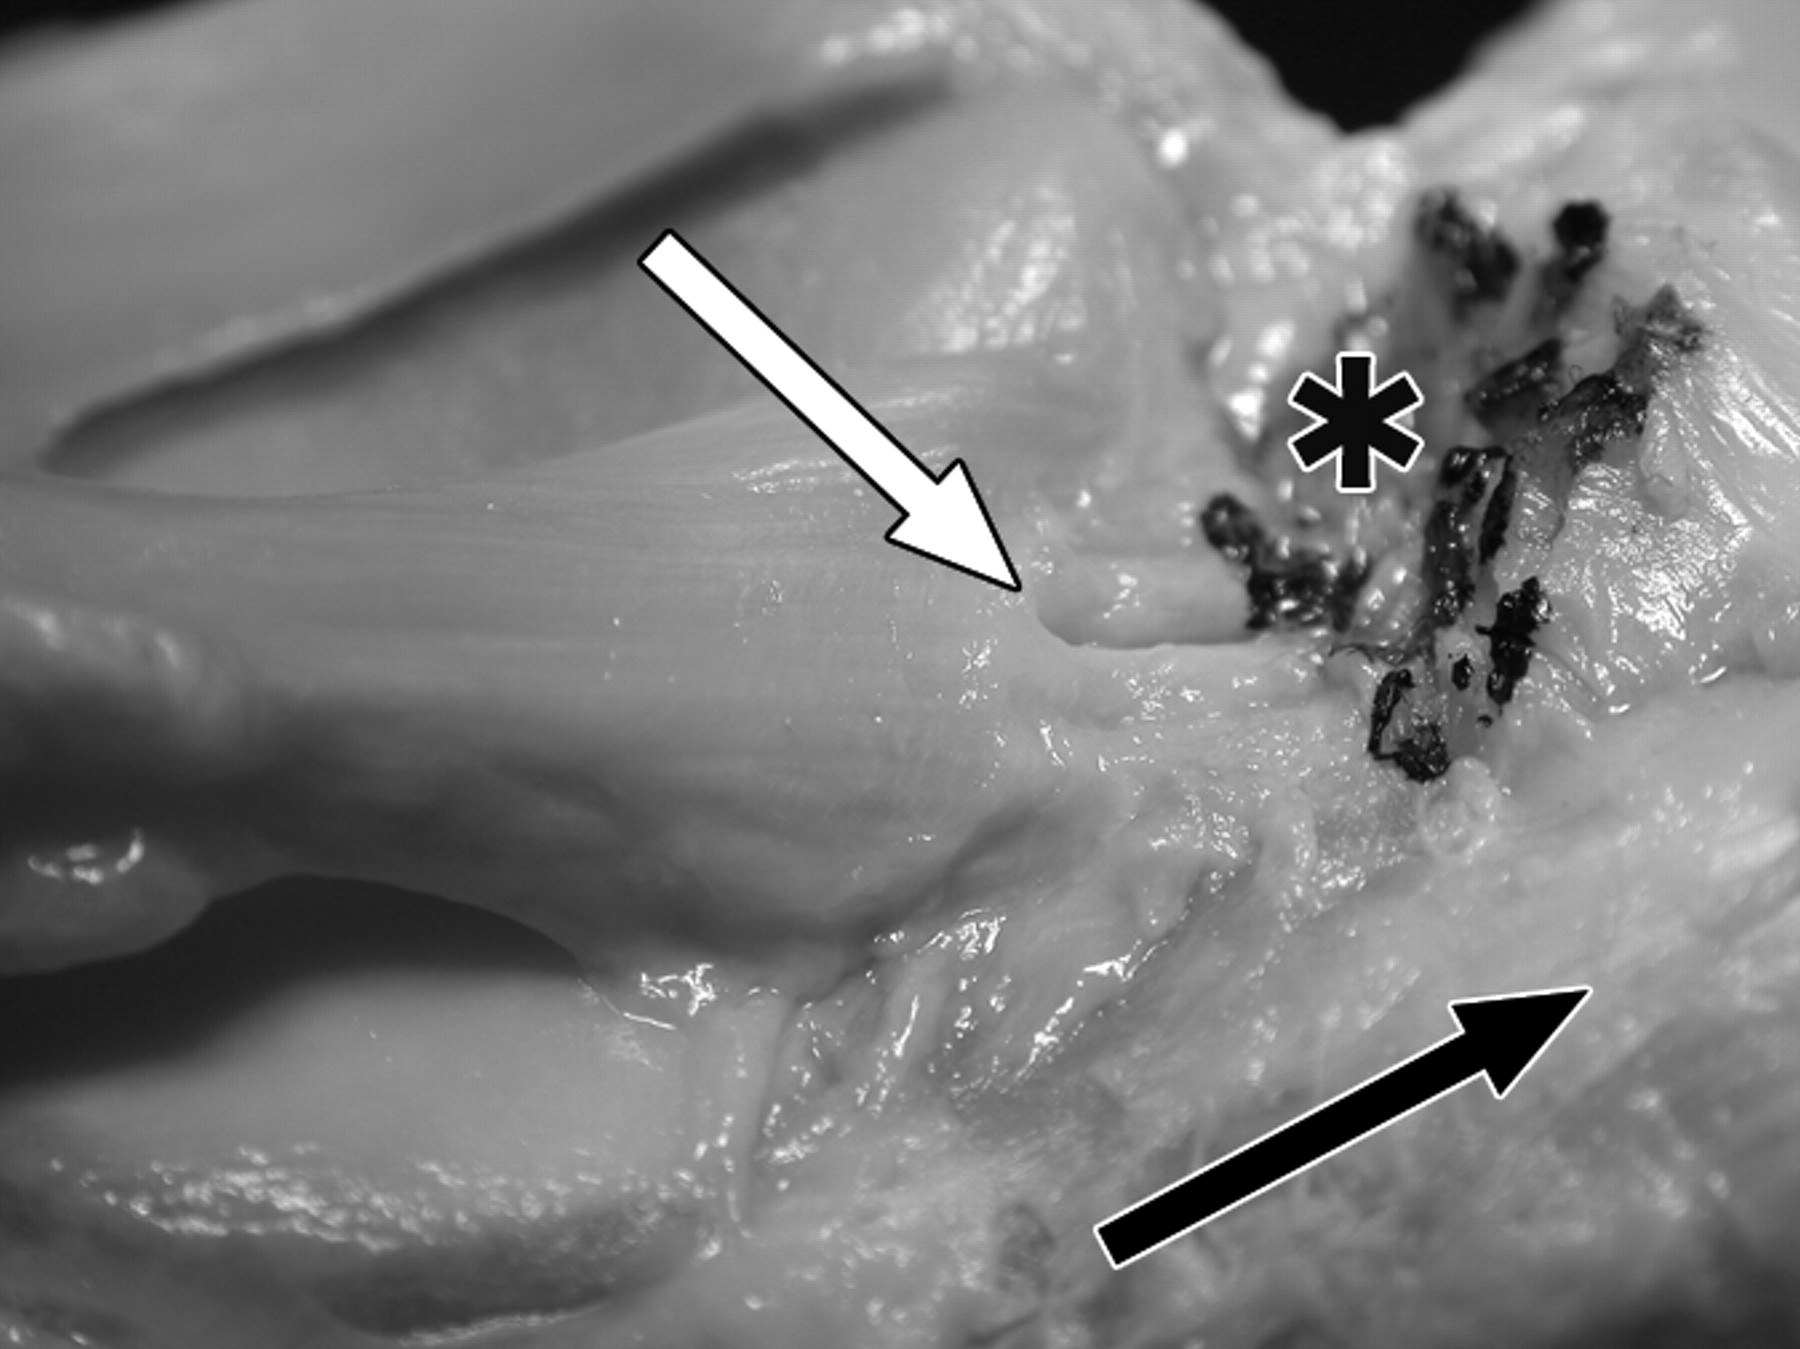

876e6aa3ed959ec44608ba1418643771.jpeg

图4 B-59岁男性大体标本。

照片显示了前、后交叉韧带胫骨止点的解剖关系。

膝关节后视图显示外侧半月板后根(LM)(白色箭头)的止点比内侧半月板后根(MM)(黑色箭头)和后交叉韧带(P)的止点更靠前。前交叉韧带止点(星号)在结节间嵴的前面,但由于摄影变形,看起来更靠近外侧半月板后根。